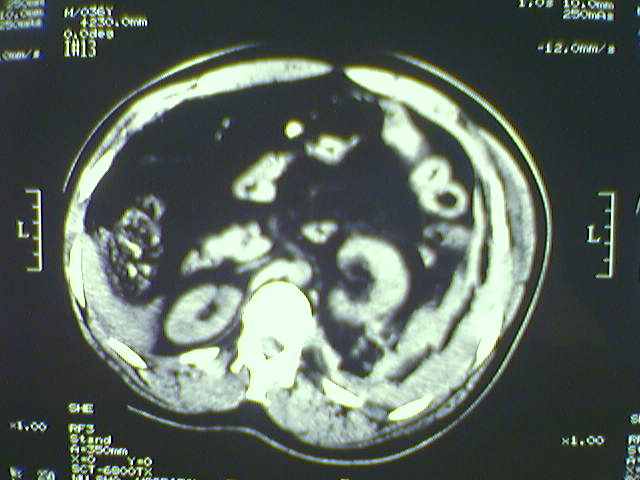

以下是引用zjzjr在2008-6-3 21:01:00的发言:[br]腹腔积液+邻近软组织肿厚.考虑感染性病变可能性大.